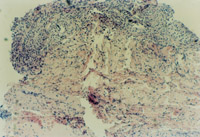

3-23 對(duì)其“皮點(diǎn)”進(jìn)行組織學(xué)檢查,該組織為從皮下組織中再生出的微血管、膠原組織、表皮細(xì)胞組織組成的再生皮膚組織團(tuán)

3-24 該“皮點(diǎn)”逐漸擴(kuò)展為皮膚組織團(tuán),各皮膚組織團(tuán)互相融合